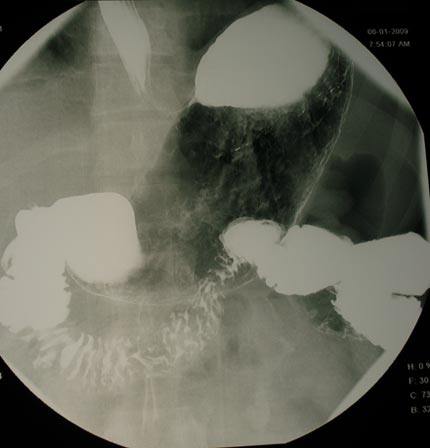

X-ray image of a patient's stomach during an upper GI exam.

Note: Images are shown for illustrative purposes. Do not attempt to draw conclusions or make diagnoses by comparing these images to other medical images, particularly your own. Only qualified physicians should interpret images; the radiologist is the physician expert trained in medical imaging.